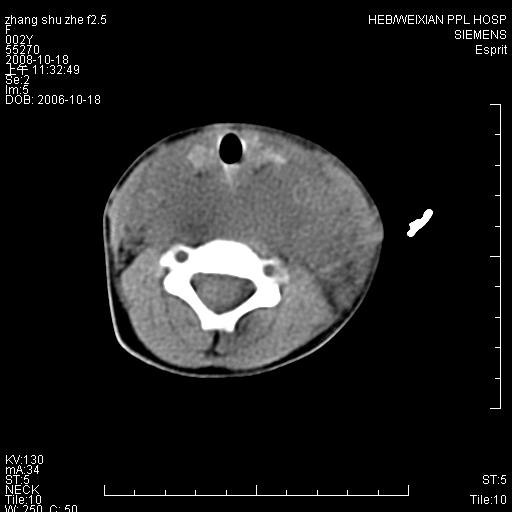

以下是引用dyqct在2009-2-10 21:04:00的发言:[br]年龄?性别?有发烧吗?[br]鼻咽部、口咽部、喉咽部及颈椎前间隙广泛肿厚,明显占位效应并致相应组织变形。ct值22-28hu。[br]考虑:1、颈前脓肿可能性大;[br] 2、建议增强或治疗后复查。

以下是引用jiangjing在2009-2-11 11:37:00的发言:[br]急性病程,鼻咽部、口咽部、喉咽部及颈椎前间隙广泛肿厚,明显占位效应并致相应组织变形.考虑颈部感染性病变(脓肿?);建议行进一步检查。